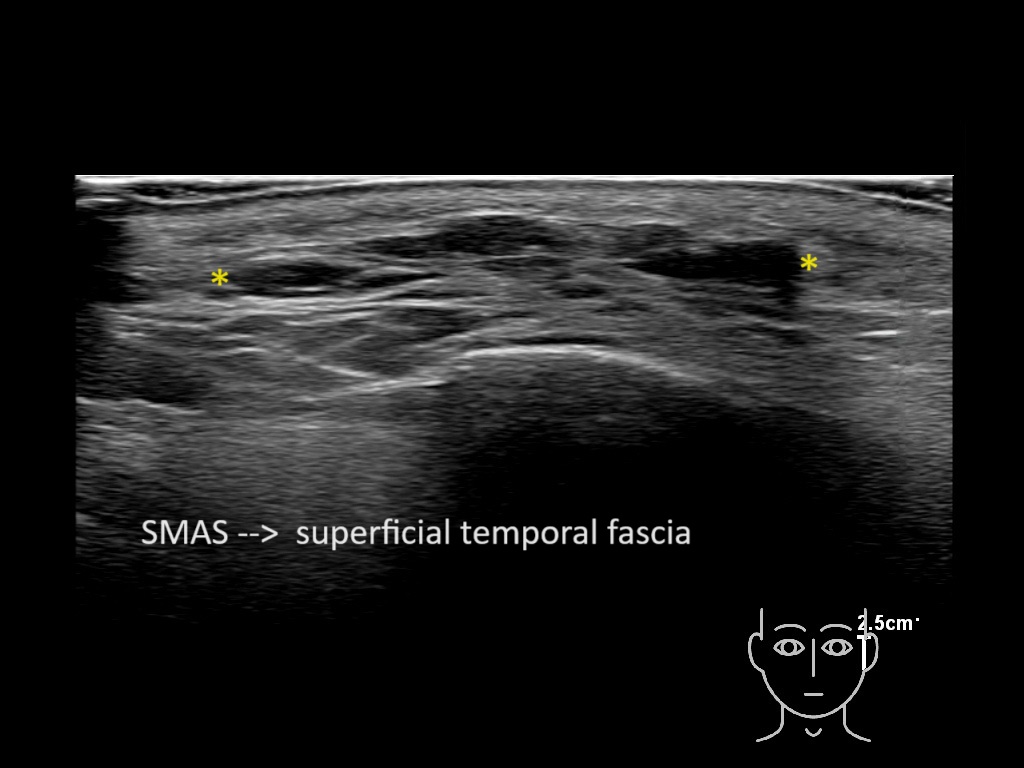

Filler behavior - Temple zygoma US

Study the first image to recognize the different layers. If you are sure about the layers, swipe to the second image to view the answer (if applicable).

Hover over an image to view the secondary image or click on the image title for more information.